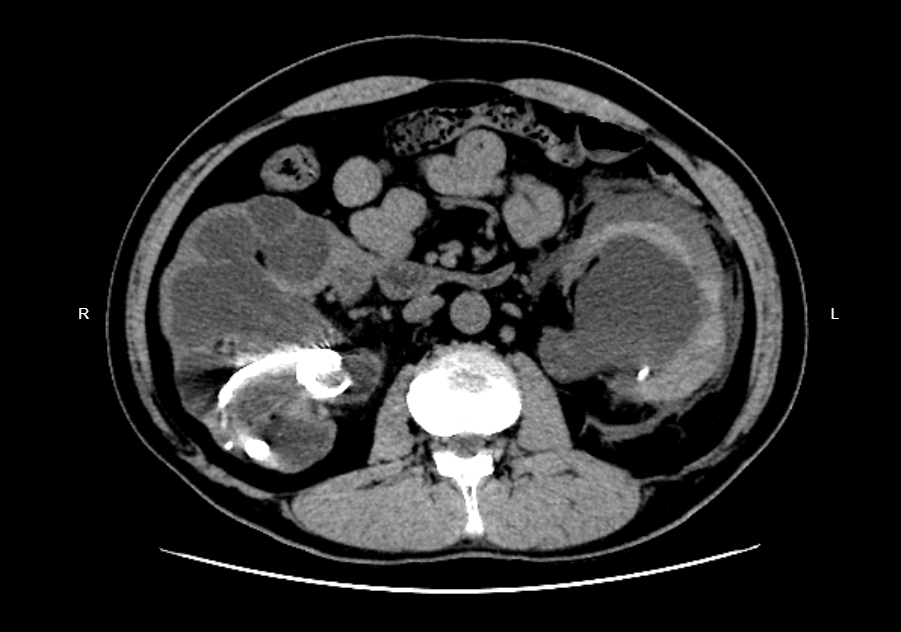

5月18日入院的一位患者,病例編號:BL001。持續(xù)更新該患者后續(xù)治療過程。時間引導(dǎo)線:2024年5月18日入院:右側(cè)雙J管留置8年,雙腎、輸尿管多發(fā)結(jié)石,雙腎極重度積水,左腎包膜下血腫,腎功能不全,急性腎盂腎炎,發(fā)熱40度。2024年5月19日急診行經(jīng)尿道左輸尿管支架置入+右腎穿刺引流術(shù)。2024年5月21日腹部平片提示右側(cè)輸尿管內(nèi)為兩根雙J管,其中一根已斷成3段。2024年5月29日全麻下行經(jīng)尿道膀胱鈥激光碎石(雙J管表面)+膀胱段雙J管取出+腹腔段雙J管②取出+左輸尿管支架置入+右側(cè)經(jīng)皮腎鏡碎石+右側(cè)輸尿管支架①拔除+輸尿管支架②腎臟段取出+右側(cè)輸尿管支架置入。輸尿管支架取出并置換全過程手術(shù)視頻2024年5月31日CT可見左腎包膜下積血已液化,對左腎組織壓迫嚴(yán)重,左腎周滲出較前明顯。2024年6月4日患者持續(xù)左腰痛,低熱,考慮與左腎包膜下血腫有關(guān)。超聲引導(dǎo)下行左腎包膜下血腫穿刺,抽出積血340ml。穿刺前超聲下已難以辨別腎臟形態(tài),穿刺后,壓迫解除,腎臟形態(tài)逐漸清晰。2024年6月5日拔除右腎造瘺管。2024年6月6日拔除導(dǎo)尿管。2024年6月7日出院。擬1月后返院,處理左側(cè)輸尿管及左腎結(jié)石。詳細(xì)病情:患者,男,47歲,8年前于上海某醫(yī)院行右腎結(jié)石手術(shù)(開放),術(shù)后右側(cè)輸尿管支架置入,后醫(yī)生告知需長期留置雙J管,或選擇行腎造瘺(具體原因不詳,估計是輸尿管狹窄),患者選擇留置雙J管,術(shù)后2月成功更換1次,醫(yī)生告知此管可留置1年。不到1年時,患者前去更換,更換失敗,醫(yī)生告知無法拔出(患者如此陳述,具體不詳)。后輾轉(zhuǎn)多家醫(yī)院,未果,一直留置至今。2024年4月11日就診我院,CT提示雙腎重度積水,皮質(zhì)變薄,左腎尚無包膜下出血,具體如下。門診醫(yī)生建議上級醫(yī)院進(jìn)一步治療。(患者未行治療)2024年5月18日凌晨3點(diǎn),突然出現(xiàn)左側(cè)腰腹部疼痛,持續(xù)性絞痛,稍劇尚可忍,伴發(fā)熱,體溫最高40℃,無寒戰(zhàn)肢冷,無惡心嘔吐。就診我院急診,CT、血常規(guī)、腎功能(Cr188umol/L)結(jié)果如下。擬“泌尿系結(jié)石”收住入院。入院測體溫37.5℃,左側(cè)腰痛明顯,予止痛治療后好轉(zhuǎn)。查尿白細(xì)胞:1731/ul。PCT:12ng/ml。目前予舒普深抗感染、止血、絕對臥床休息等對癥治療。I期處理方案2024年5月19日復(fù)查肌酐:217umol/L,血白細(xì)胞:10.11×10^9/L,CRP:211mg/L。持續(xù)左腰腹疼痛。急診行經(jīng)尿道左輸尿管支架置入+右腎穿刺引流術(shù),備左腎穿刺引流術(shù)(經(jīng)尿道左輸尿管支架置入失敗后選擇)。經(jīng)尿道輸尿管鏡下左輸尿管支架置入術(shù),進(jìn)入膀胱,見膀胱內(nèi)尿液渾濁,右側(cè)輸尿管支架表面完全被結(jié)石覆蓋,左側(cè)輸尿管開口結(jié)石堵塞,經(jīng)反復(fù)推頂,略有松動后,置入導(dǎo)絲,該結(jié)石松動退回至輸尿管,導(dǎo)絲引導(dǎo)下置入6F雙J管順利。留置導(dǎo)尿,尿液為膿白色。具體手術(shù)過程如下:右腎穿刺引流過程:2024年5月20日:術(shù)后至次日生命體征均平穩(wěn),左側(cè)腰痛緩解。復(fù)查血白細(xì)胞,肌酐較前降低(217umol/L將至177umol/L)。美羅培南抗感染治療。2024年5月21日:尿培養(yǎng):優(yōu)美顆粒鏈菌,美羅培南敏感。復(fù)查尿常規(guī)WBC3386/ul。繼續(xù)美羅培南抗感染。查腹部臥位平片,才發(fā)現(xiàn)原來右輸尿管內(nèi)留置的雙J管為兩根,其中一根已斷為3截,一段在腎臟,一段在輸尿管,一段在膀胱。影像圖片如下:雙J管2已自然斷裂,術(shù)中可能鉗夾困難,難以完整取除。這無疑又增加了手術(shù)難度。II期處理2024年5月29日全麻下行:先截石位:經(jīng)尿道膀胱鈥激光碎石(雙J管表面)+膀胱段雙J管取出+腹腔段雙J管②取出+左輸尿管支架置入改90°左側(cè)臥位:右側(cè)經(jīng)皮腎鏡(通道22F)雙J管表面碎石+右側(cè)輸尿管支架①拔除+輸尿管支架②腎臟段取出+右腎下極大量橢圓形結(jié)石碎石取石。經(jīng)腎鏡通道,見腎盂輸尿管交界處扭曲、黏膜增生水腫,無法找到正常通道。改截石位:輸尿管鏡沿右側(cè)輸尿管上行通過盂管交界處狹窄,進(jìn)入腎臟,導(dǎo)絲引導(dǎo)下置入6F腫瘤支架管1根。取出的兩根右側(cè)輸尿管支架,輸尿管支架①原為完整1根,于輸尿管開口處激光截斷,故為2段。輸尿管支架②為三段:膀胱段、腹腔段、腎內(nèi)段。支架管①支架管②2024年5月31日(夾閉右腎造瘺管狀態(tài)下)CT可見右腎積水明顯緩解,右腎多發(fā)結(jié)石(較前減少),右側(cè)輸尿管支架位置正常。但左腎包膜下積血已液化,對左腎組織壓迫嚴(yán)重,左腎周滲出較前明顯。2024年6月4日患者持續(xù)左腰痛,低熱,考慮與左腎包膜下血腫有關(guān)。超聲引導(dǎo)下行左腎包膜下血腫穿刺,抽出積血約340ml。穿刺前超聲下已難以辨別腎臟形態(tài),穿刺后,壓迫解除,腎臟形態(tài)逐漸清晰。穿刺后腰痛緩解,體溫恢復(fù)正常:2024年6月5日拔除右腎造瘺管。2024年6月6日拔除導(dǎo)尿管。2024年6月7日出院,總共花費(fèi)約3萬元。III期處理擬1月后處理左側(cè)輸尿管及左腎結(jié)石。持續(xù)更新,歡迎關(guān)注。